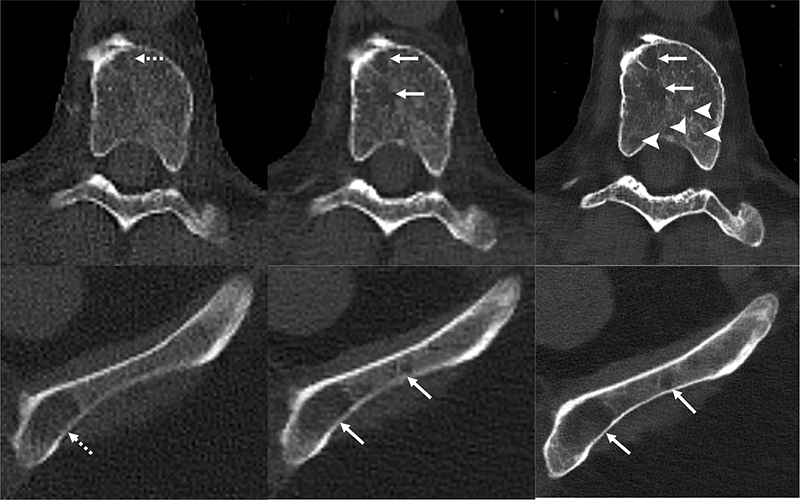

Рис. 5 Баффур

Изображения 71-летнего мужчины с множественной миеломой. Литические поражения (пунктирные стрелки) в теле грудного позвонка и левом крыле подвздошной кости более заметны на КТ-изображении с аксиальным детектором счета фотонов (PCD) без контрастного усиления (в центре; сплошные стрелки) по сравнению с аксиальным детектором с интеграцией энергии без контрастного усиления. КТ-изображение (слева). На аксиальных КТ-реконструкциях PCD с 0,6-мм Br76 без контрастного усиления (справа) было обнаружено больше поражений (указатели стрелок).